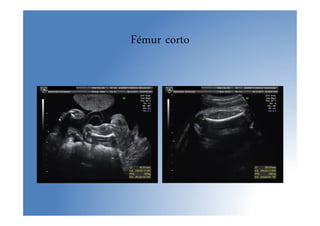

• Signo de alarma: Fémur corto (p<5 para EG, <

2DE)

• La mayoría de los LF cortos aislados son

constitucionales

• Displasia: LF < 4 DE. Sino: controles seriados

Fémur corto